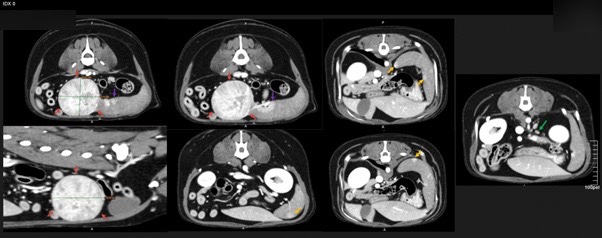

정확한 진단을 위해 본원에서 CT 검사를 진행하였습니다.

강아지 비장종양 CT 검사 결과 / 출처: 에스동물메디컬센터

CT 주요 소견

비장 꼬리 부분에서 4.4 x 4.0 x 3.5cm 크기

둥글고 경계가 뚜렷한 종괴 확인

내부는 이질적이며 조영제에 뚜렷하게 반응

이 혹은 비장종양, 조혈기능 과다, 림프조직 증식 등 가능성

​주변 비장 조직에도 작은 병변 등이 관찰되어 조직검사 권장

​인근 림프절이 약간 커져 있었으나(3.8mm),

염증 반응인지 전이 가능성인지는 불분명